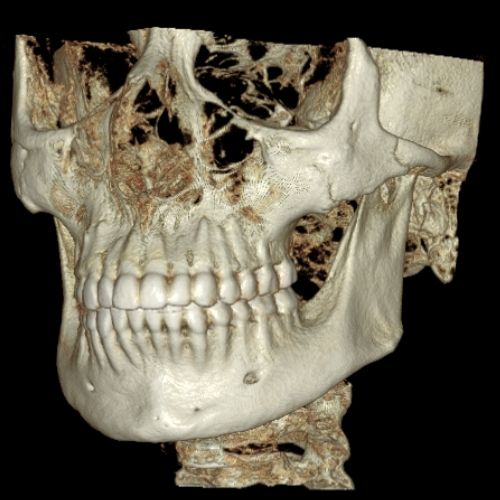

Slab and Cutting

Slab Feature allows the clinician to see inside structures while rotating the 3D image. Cut away structures to see exactly what is pertinent to your study.